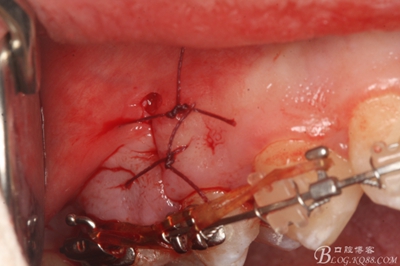

圖23.僅做頰側(cè)垂直切口縫合

圖24.合面觀:微創(chuàng)小切口,15牙根完整取出,創(chuàng)傷小。